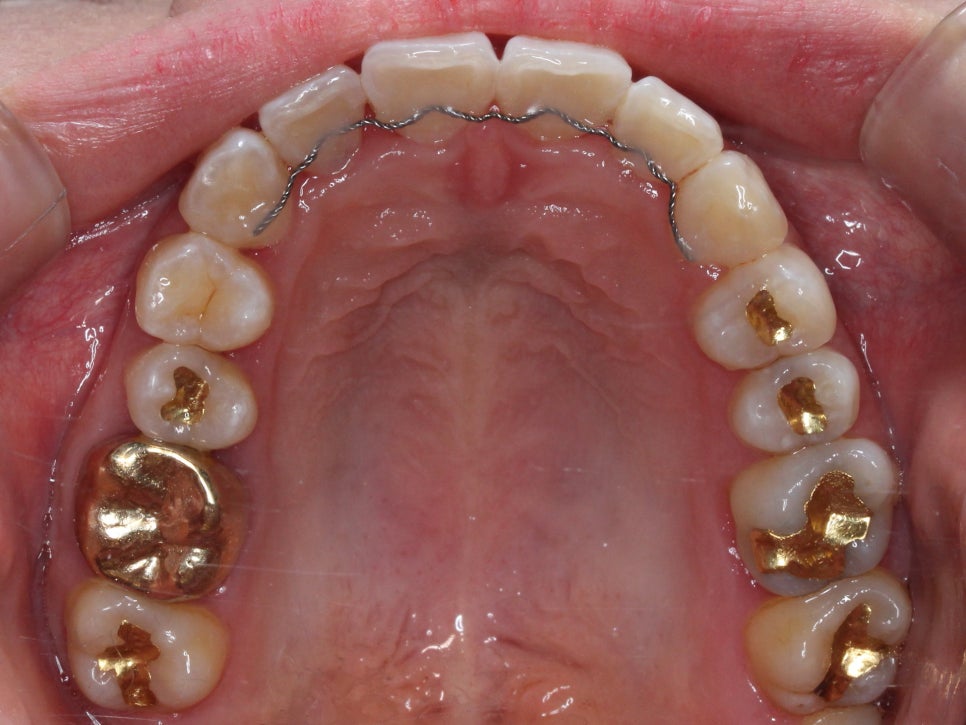

중간과정

우선 배열을 바로 잡기로 했습니다.

치아를 가지런하게 펴기 위해선

치간삭제는 필수적이었습니다.

삭제 없이 치아를 펴면

뻐드러지기 때문에

치아에 해를 끼치지 않는 선에서

치간삭제를 시행합니다.